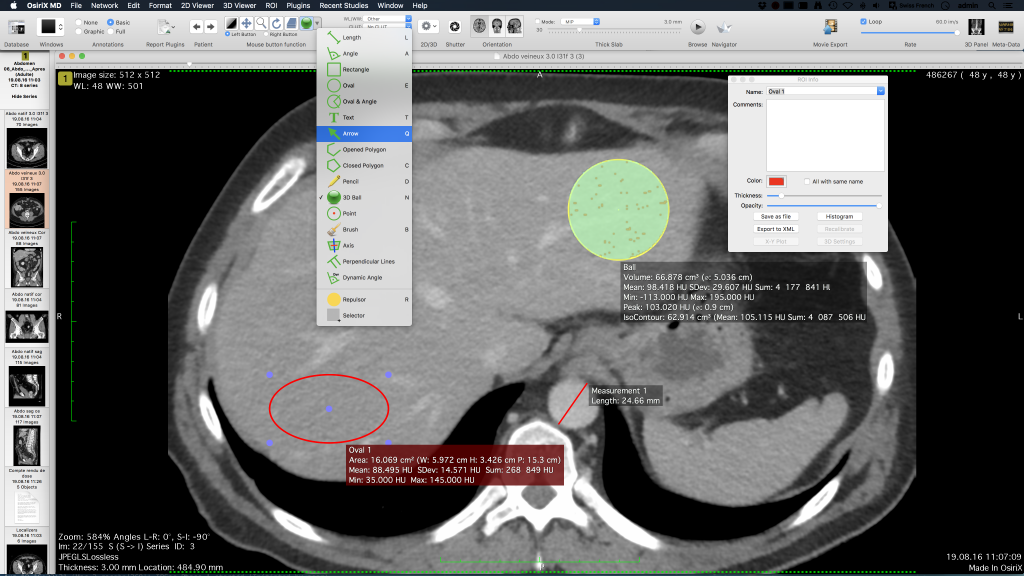

Çizgiler, çokgenler, 3B top gibi görüntülere Anahtar Görüntüler ve İlgi Alanları (ROI’ler) kolayca ekleyebilir ve bunları veritabanına kaydedebilirsiniz.

Kemik veya akciğer filtreleri gibi görüntülere kıvrım filtresi uygulayabilirsiniz.